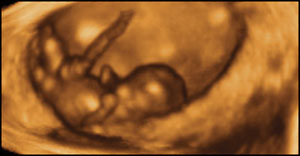

10 týdnů, 6 cm

Plod se chová stejně jako dítě po narození. Pokud je položeno, snaží se o pohyb dopředu.